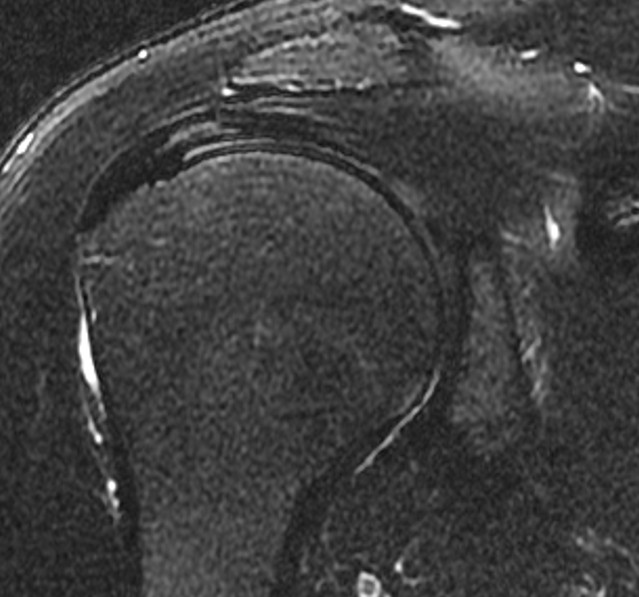

수개월간 지속되던 우측 어깨통증으로 꾸준한 보존적 치료(약물,주사,충격파,도수재활치료 등)을 시행하였으나 증상이 호전되지 않고, 점차 팔을 옆으로 들때나 뻗을때 통증이 심해지고, 팔을 옆으로 들어 밖으로 돌릴때 더 통증이 심해지는 양상. 방문한 병원에서는 석회가 조금 있고, 회전근개주위 염증이 있으며, 뼈가 자라서 힘줄을 손상시킨다는 진단을 받음. 이후로 재생주사,스테로이드 주사치료도 병행하였으나 증상이 호전되지 않고, 움직일때마다 통증때문에 팔에 힘을 주기가 어려워짐. 시술전(pre) MRI검사상 회전근개 위쪽(점액낭쪽)으로 힘줄염과 회전근개 일부가 벗겨진 부분손상이 확인되어 더핌스 축소봉합술을 시행함. 시술후(post) 시행한 MRI상 손상되었던 힘줄이 회복되었음이 확인되었고, 시술후 바로 일상생활/직장생활로 복귀하였으며, 어깨를 움직일때마다 발생했던 통증이 사라짐.